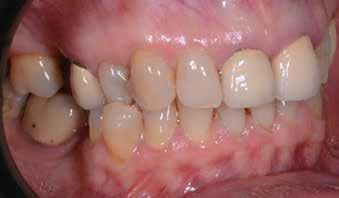

A 26 éves férfi páciens azzal a kéréssel kereste fel a rendelőnket, hogy a frontfogai esztétikusabb megjelenését szeretné elérni. A páciens jó általános egészségi állapottal rendelkezett, nem szenvedett allergiáktól és nem kellett rendszeresen gyógyszereket szednie. A páciens lehetőség szerint kerülte a fogai megmutatását. Rendkívül zavarónak találta a nagymetszői között, a középvonalnak megfelelően látható rést, a fogain látható kopási jeleket, valamint a fogai méretét is túl kicsinek találta. A szájüregi vizsgálat során megállapítottuk, hogy a nagymetsző fogai (11, 21) élharapásban vannak, valamint az alsó fogíven kismértékű torlódást észleltünk. A felső frontfogakon

(13-23) attrícióra utaló jeleket találtunk. A fogak kopása a nagymetszőfogaknak megfelelően volt a legkifejezettebb (1. ábra) . Az előbbiekben említett fogak (11, 21) ezen kívül némileg elfordultak, és jelentősebb méretű diasztéma volt köztük. A páciens Angle I.-osztályú állcsontrelációs helyzettel rendelkezett. A vizsgálat során feltűnt, hogy a páciens csak nagyon óvatosan mert mosolyogni (2. ábra)

A szájüregi vizsgálat során nem találtunk szuvas léziók jelenlétére utaló eltéréseket. A nagymetszőfogakon megfigyelhető jelentős mértékű kopás ellenére nem észleltünk craniomandibuláris diszfunkció jelenlétére utaló jeleket. A vizsgálat befejezését követően a pácienst tájékoztattuk a különböző kezelési lehetőségekről. Az esztétikai megjelenés javítása érdekében először egy alignerekkel végzett fogszabályzó kezelés elvégzését, majd a harapási helyzet optimalizálását követően a felső frontfogai kompozittal történő direkt felépítését vagy héjakkal történő ellátását (pl.: non-prep héjak) javasoltuk (3. és 4. ábra).

A fogazat minimálinvazív módon készített héjakkal történő ellátásához a fogaknak olyan pozícióban kell lenniük, amely lehetővé teszi az esztétikai megjelenés additív eljárások alkalmazása mellett történő optimalizálását.1. ábra: Kiindulási állapot. A felső nagymetszőfogak élharapásban vannak. 2. ábra: Az orthodonciai kezelés megkezdése előtt készített intraorális felvétel. A páciens csak óvatosan mer mosolyogni. 3. és 4. ábra: Digitálisan megtervezett kezelés.

A kezelések második fázisában a pácienssel közösen non-prep/ minimálinvazív héjak készítése mellett döntöttünk (6. és 7. ábra).

A páciens teljesen elégedett volt a kezelések befejezését követően elért esztétikai végeredménnyel (9. ábra). A terápiás erőfeszítéseink eredményeinek köszönhetően újra képes felszabadultan nevetni és mosolyogni. A cikkben bemutatásra kerülő eset jól példázza a multidiszciplináris beavatkozások alkalmazásában rejlő előnyöket. A megfelelő sorrendben végzett orthodonciai és restauratív kezelésekkel lehetővé vált a páciens mosolyának minimálinvazív módszerekkel történő optimalizálása. A körültekintő tervezésnek köszönhetően nem került sor felesleges beavatkozások elvégzésére, és emiatt a kezelések befejezéséhez szükséges idő sem nyúlt a szükségesnél hosszabbra. Arra is felhívnánk a figyelmet, hogy a jól megszervezett, továbbá a lehető legkevesebb rendelési időt felhasználó kezelések – a beavatkozásokat végző fogorvosok számára is – rendkívül kedvezőek lehetnek.